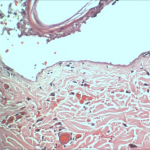

- Histopathology, by our in-house histopathology lab

- Histomorphometry/digital image analysis